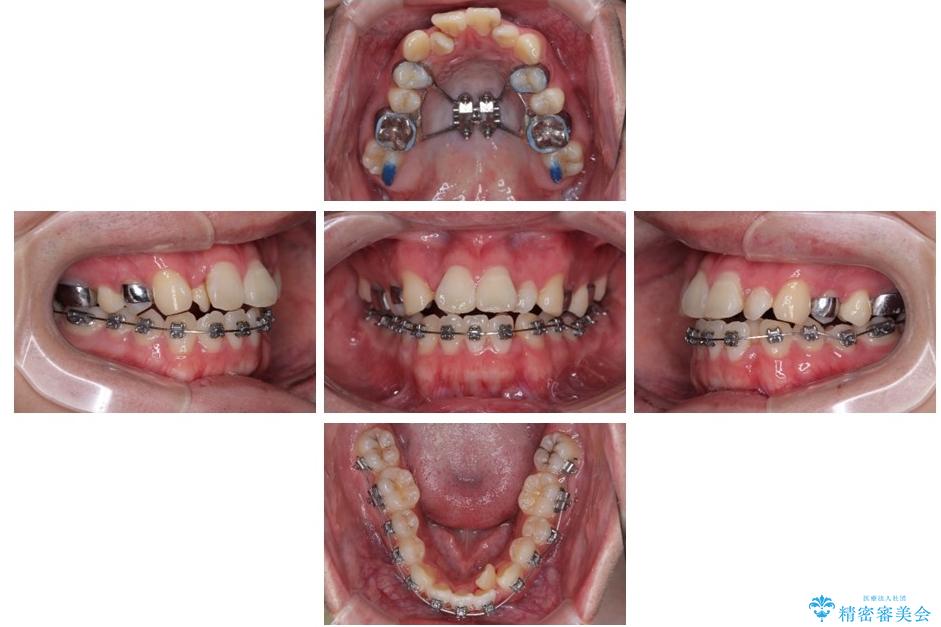

初診時の状態

・上下ともに歯がきれいに並びきらず、がたつきが見られました。

・上下の前歯の中心(正中)がずれています。

・特に上顎の幅が狭いため、下顎の歯列も内側に入り込み、歯が並ぶスペースが不足していました。

治療途中

• 1年でここまで変わる!歯列のがたつきと正中のズレを改善した矯正治療(メタルブラケット×MARPE) 治療途中画像